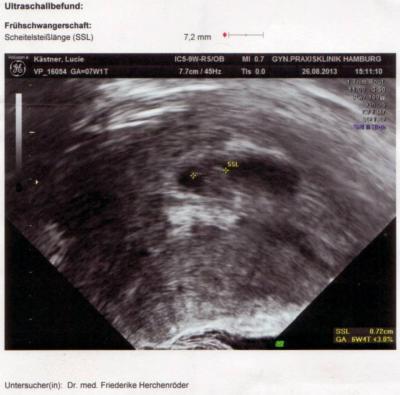

War heute wegen dem ständigen Erbrechen beim Arzt, habe das Herzchen schlagen sehen, genial.

Bild zu Mein Krümel - Forum für April - Mamis